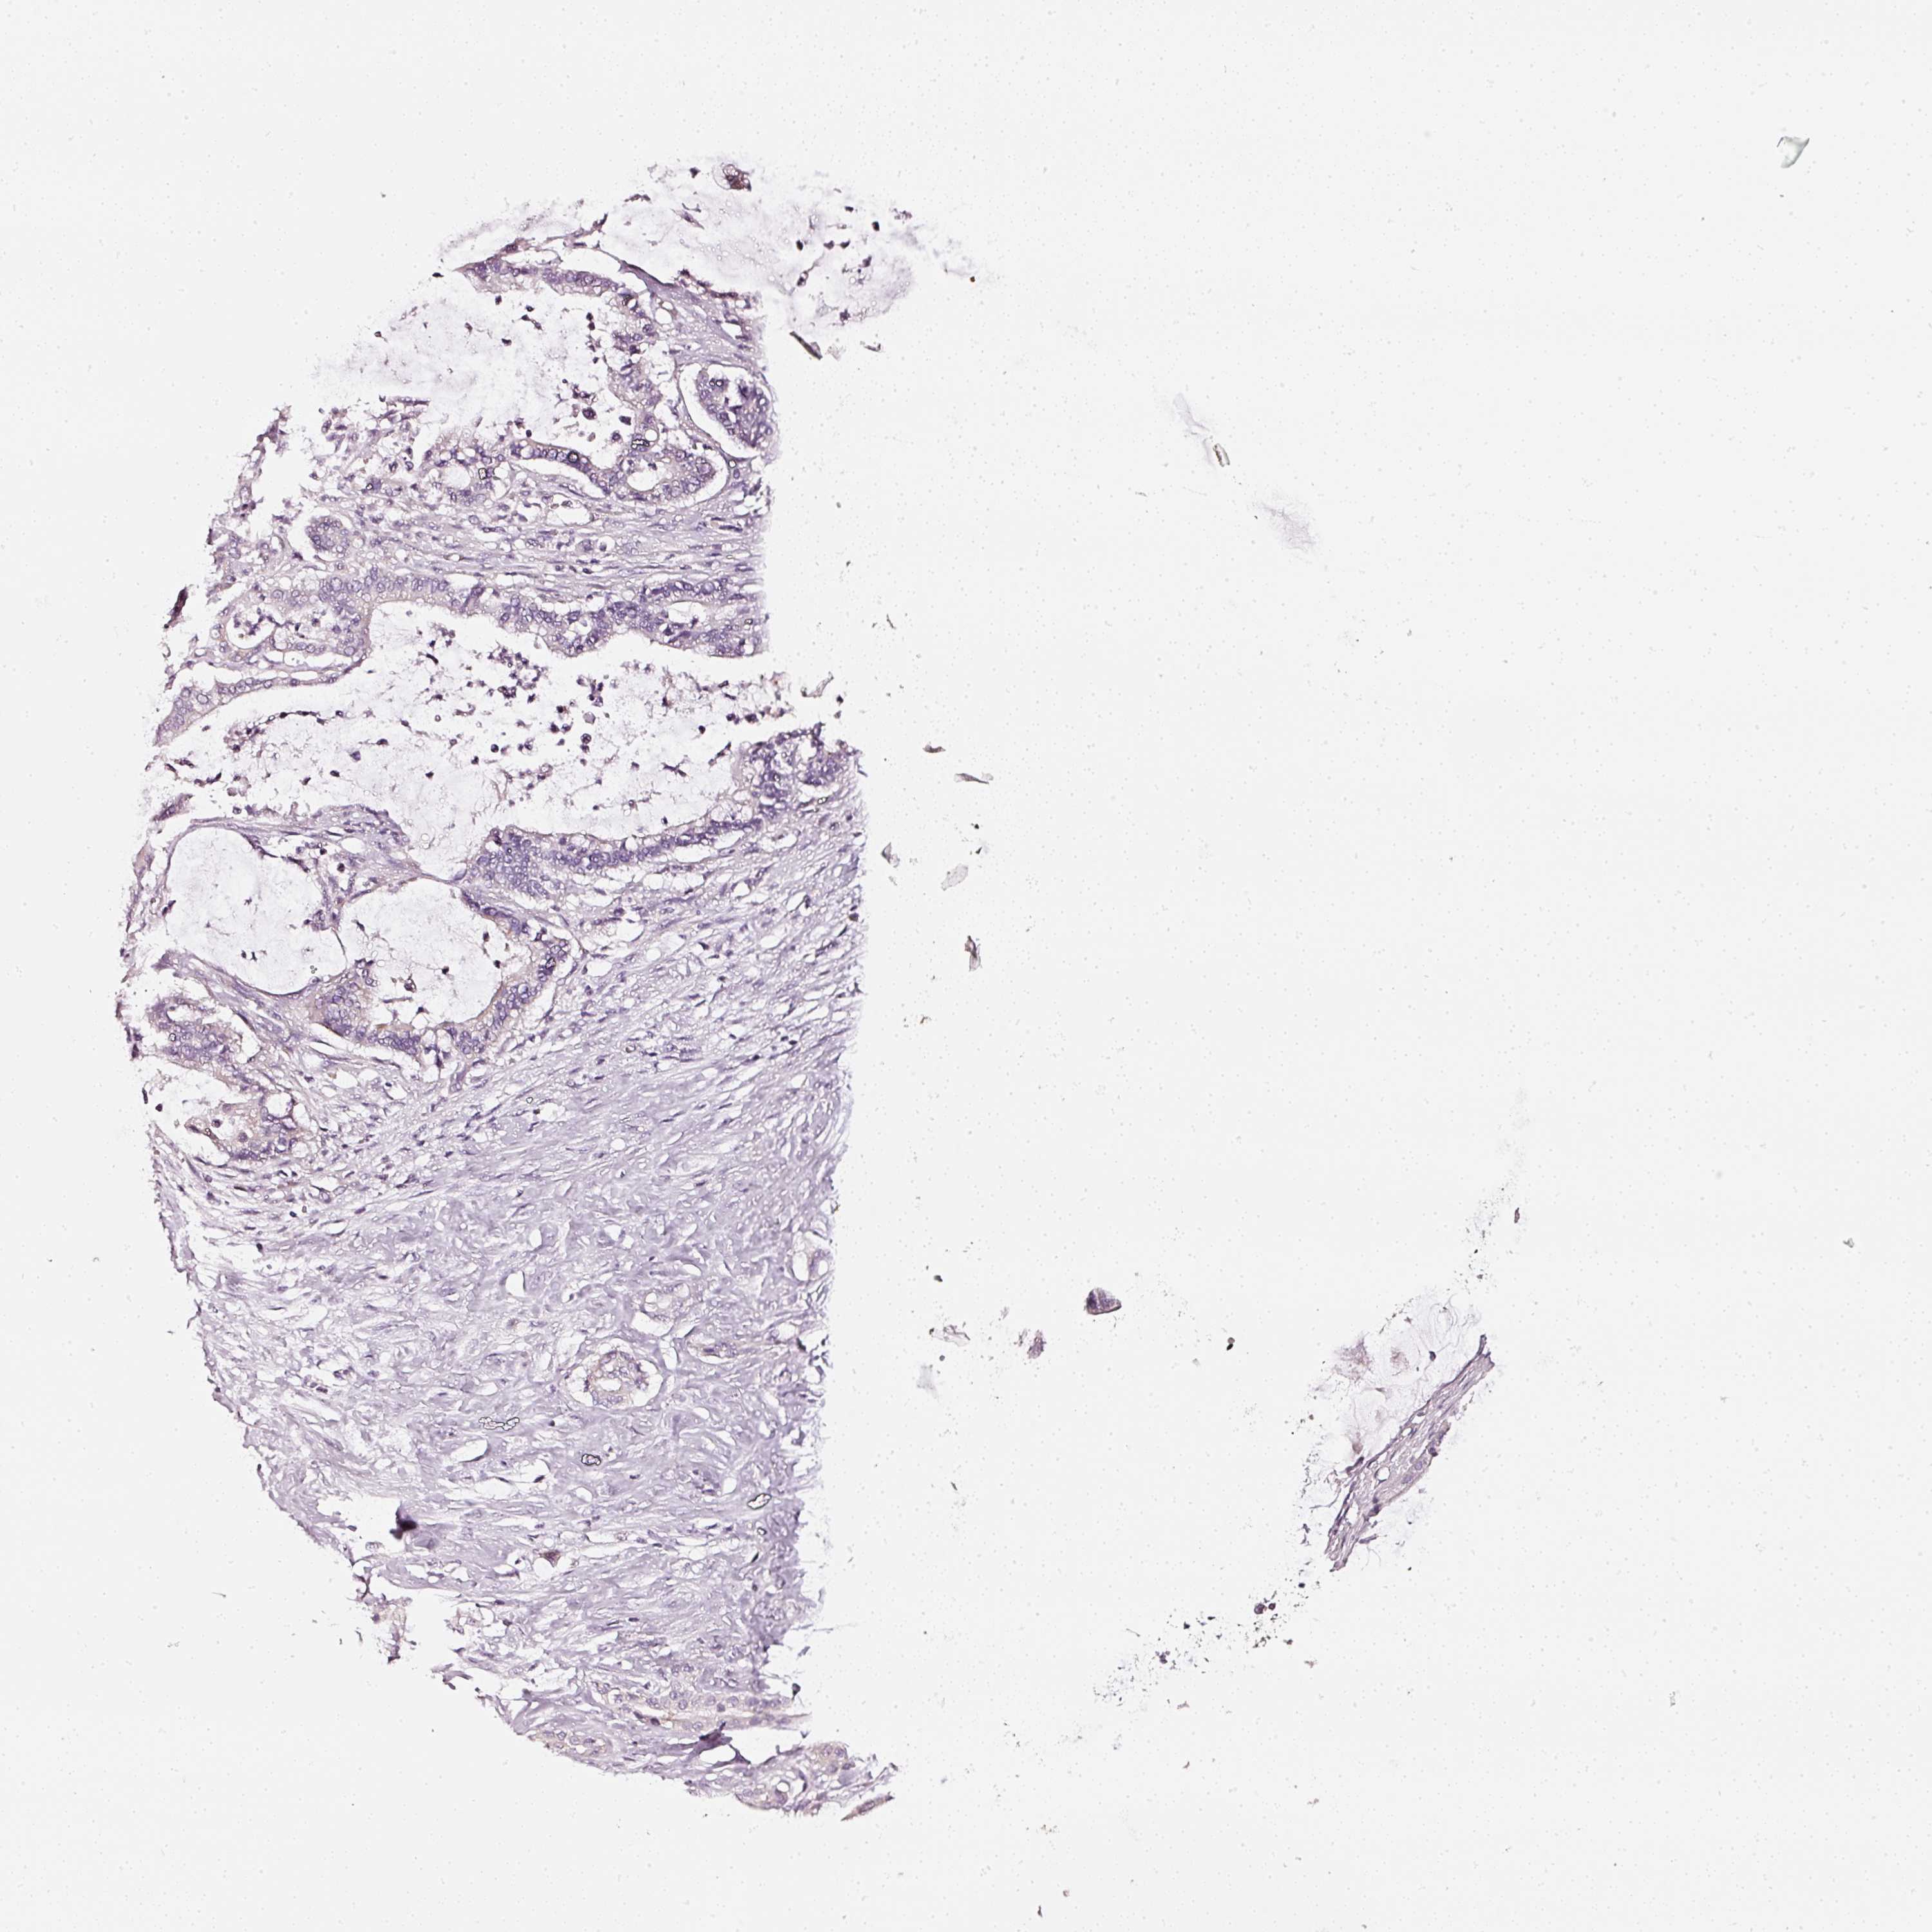

PANCREATIC CANCER - Protein expressioni

A mouse-over function shows sample information and annotation data. Click on an image to view it in a full screen mode. Samples can be filtered based on level of antibody staining by selecting one or several of the following categories: high, medium, low and not detected. The assay and annotation is described here.

Note that samples used for immunohistochemistry by the Human Protein Atlas do not correspond to samples in the TCGA dataset.

Antibody stainingi

Antibody staining in the annotated cell types in the current human tissue is reported as not detected, low, medium, or high, based on conventional immunohistochemistry profiling in selected tissues. This score is based on the combination of the staining intensity and fraction of stained cells.

Each image is clickable and will lead to virtual microscopy that enables deeper exploration of all samples and also displays staining intensity scores, fraction scores and subcellular localization as well as patient and tissue information for each sample.

HPA023266

HPA023278

HPA023280

HPA023338

CAB002672

Adenocarcinoma, NOS

Adenocarcinoma, metastatic, NOS